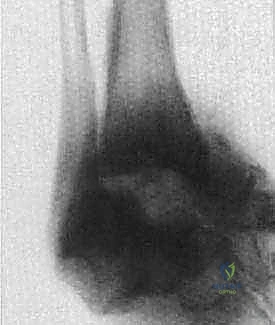

- Most commonly, the severe ankle and hindfoot deformity with talar fragmentation and resorption is seen in diabetic neuropathy. Other causes of Charcot arthropathy include tabes dorsalis, Hansen disease, syringomyelia, alcoholic neuropathy, Charcot-Marie-Tooth disease, lumbar radiculopathy, peripheral nerve lesions, Riley-Day syndrome, renal dialysis, congenital insensitivity to pain, and intra-articular steroid injections. Similar changes on radiographs can be seen in inflammatory arthritis, and in posttraumatic arthritis with talar avascular necrosis ( FIG 2 ).